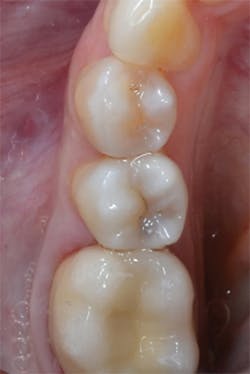

Figure 12: Final preparations on teeth Nos. 4 and 5. The Palodent Plus Sectional Matrix System has been used to isolate the MOD prep on tooth No. 4 and MO prep on tooth No. 5. The Palodent Plus Sectional Matrix System can be configured to restore multiple surfaces and multiple teeth in the same quadrant.

Figure 13: View of teeth Nos. 4 and 5 after curing the final occlusal layer of TPH Spectra composite.